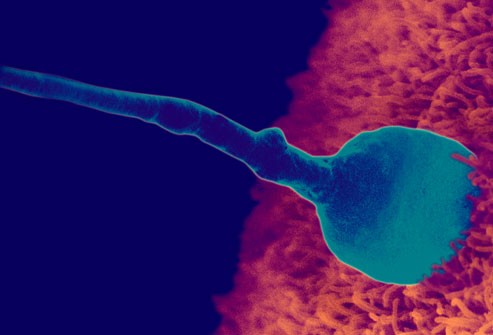

24 ساعت برای سلول اسپرم طول می کشد تا تخمک را بارور کند. زمانی که اسپرم به تخمک نفوذ می کند سطح تخمک تغییر می کند به صورتی که اسپرم دیگری نمی تواند وارد شود. در لحظه باروری, ترکیب ژنتیک کودک کامل می شود از جمله اینکه او دختر است یا پسر.